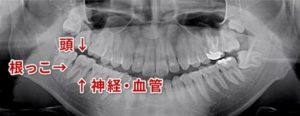

歯の神経を取ったはずなのに痛みが取れない場合は、4本目の歯の神経が見つかっていないのかもしれません

歯の神経を取ったはずなのに痛みが取れない。 治療は終了したと言われたが、どうしても痛みが取れない。 このようなことで吉本歯科医院に駆け込んで下さる患者さんがいらっしゃいます。 歯の神経の入口は 奥歯の場合 通常3つしかな […]

歯の神経治療は歯を失わないための基礎となる重要な治療

えば奥歯の神経(根っこ)の治療、保険治療では歯の神経(根っこ)は3本である、ほとんど3本であるということが、教科書に書かれております。 ですから、歯の根っこの治療(歯の神経治療)は3本までしか算定することができません。 […]